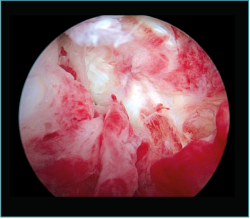

Figura 10. Caso 6. Visión artroscópica desde el portal anteromedial del engrosamiento y la hipervascularización de la cápsula anterior del codo, responsable del déficit de extensión.